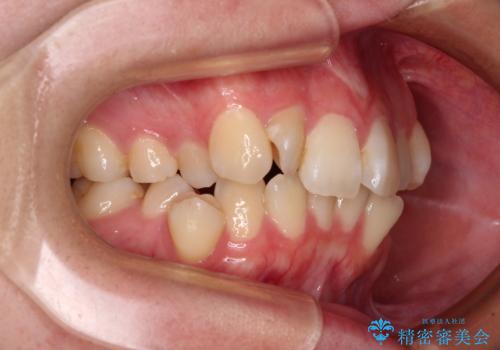

- 上下前歯のデコボコを気にして来院された患者様です。

口元の突出感はあまりなかったものの、デコボコを非抜歯で改善すると出っ歯になる可能性があるため、上下左右の第一小臼歯4本を抜歯し、ワイヤー装置にて矯正治療を行うこととしました。